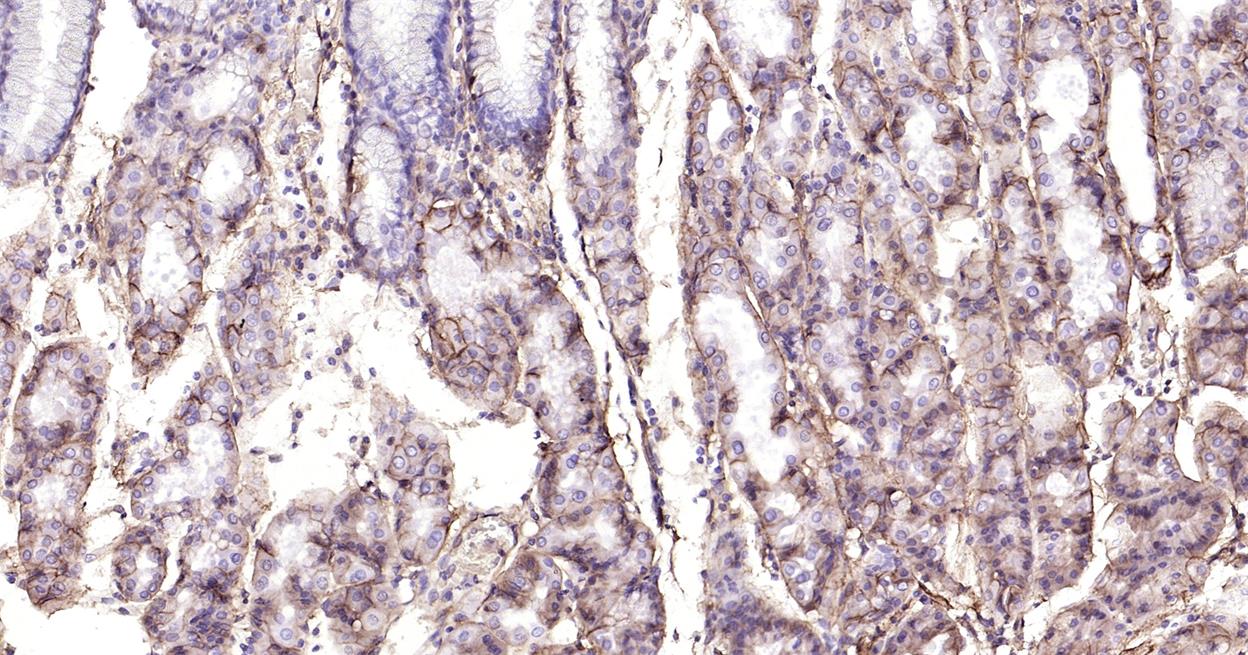

Immunohistochemical analysis of paraffin embedded human stomach tissue slide using IHC0241H (Human Integrin beta 1 IHC Kit).

Immunohistochemical analysis of paraffin embedded human colon cancer tissue slide using IHC0241H (Human Integrin beta 1 IHC Kit).

Immunohistochemical analysis of paraffin embedded human colon tissue slide using IHC0241H (Human Integrin beta 1 IHC Kit).